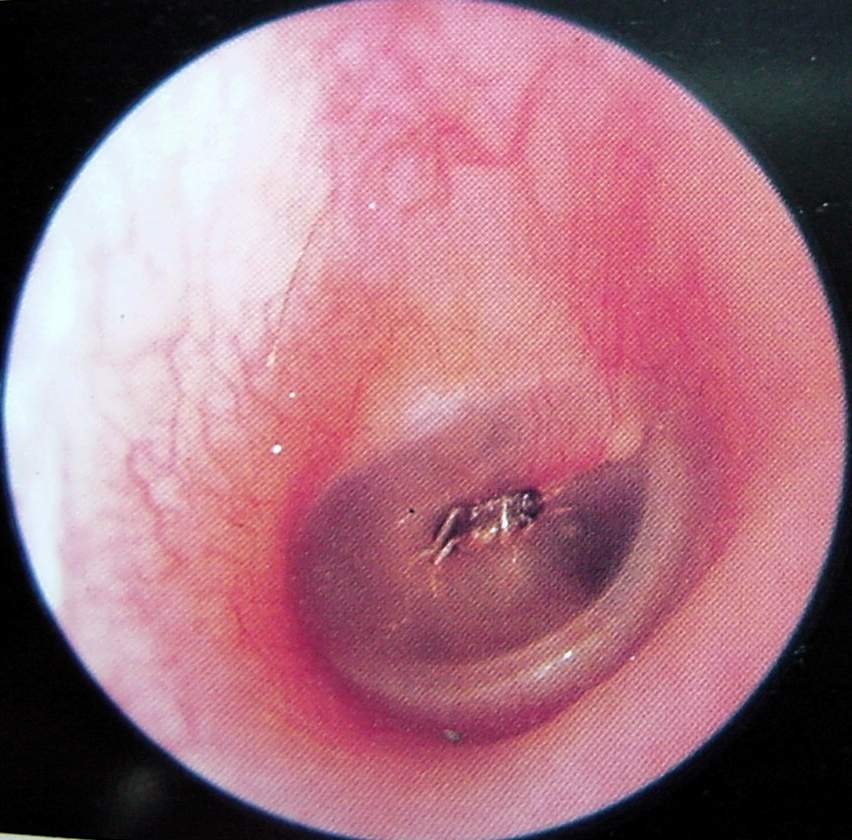

Ear Clinical Photos for Static Stations